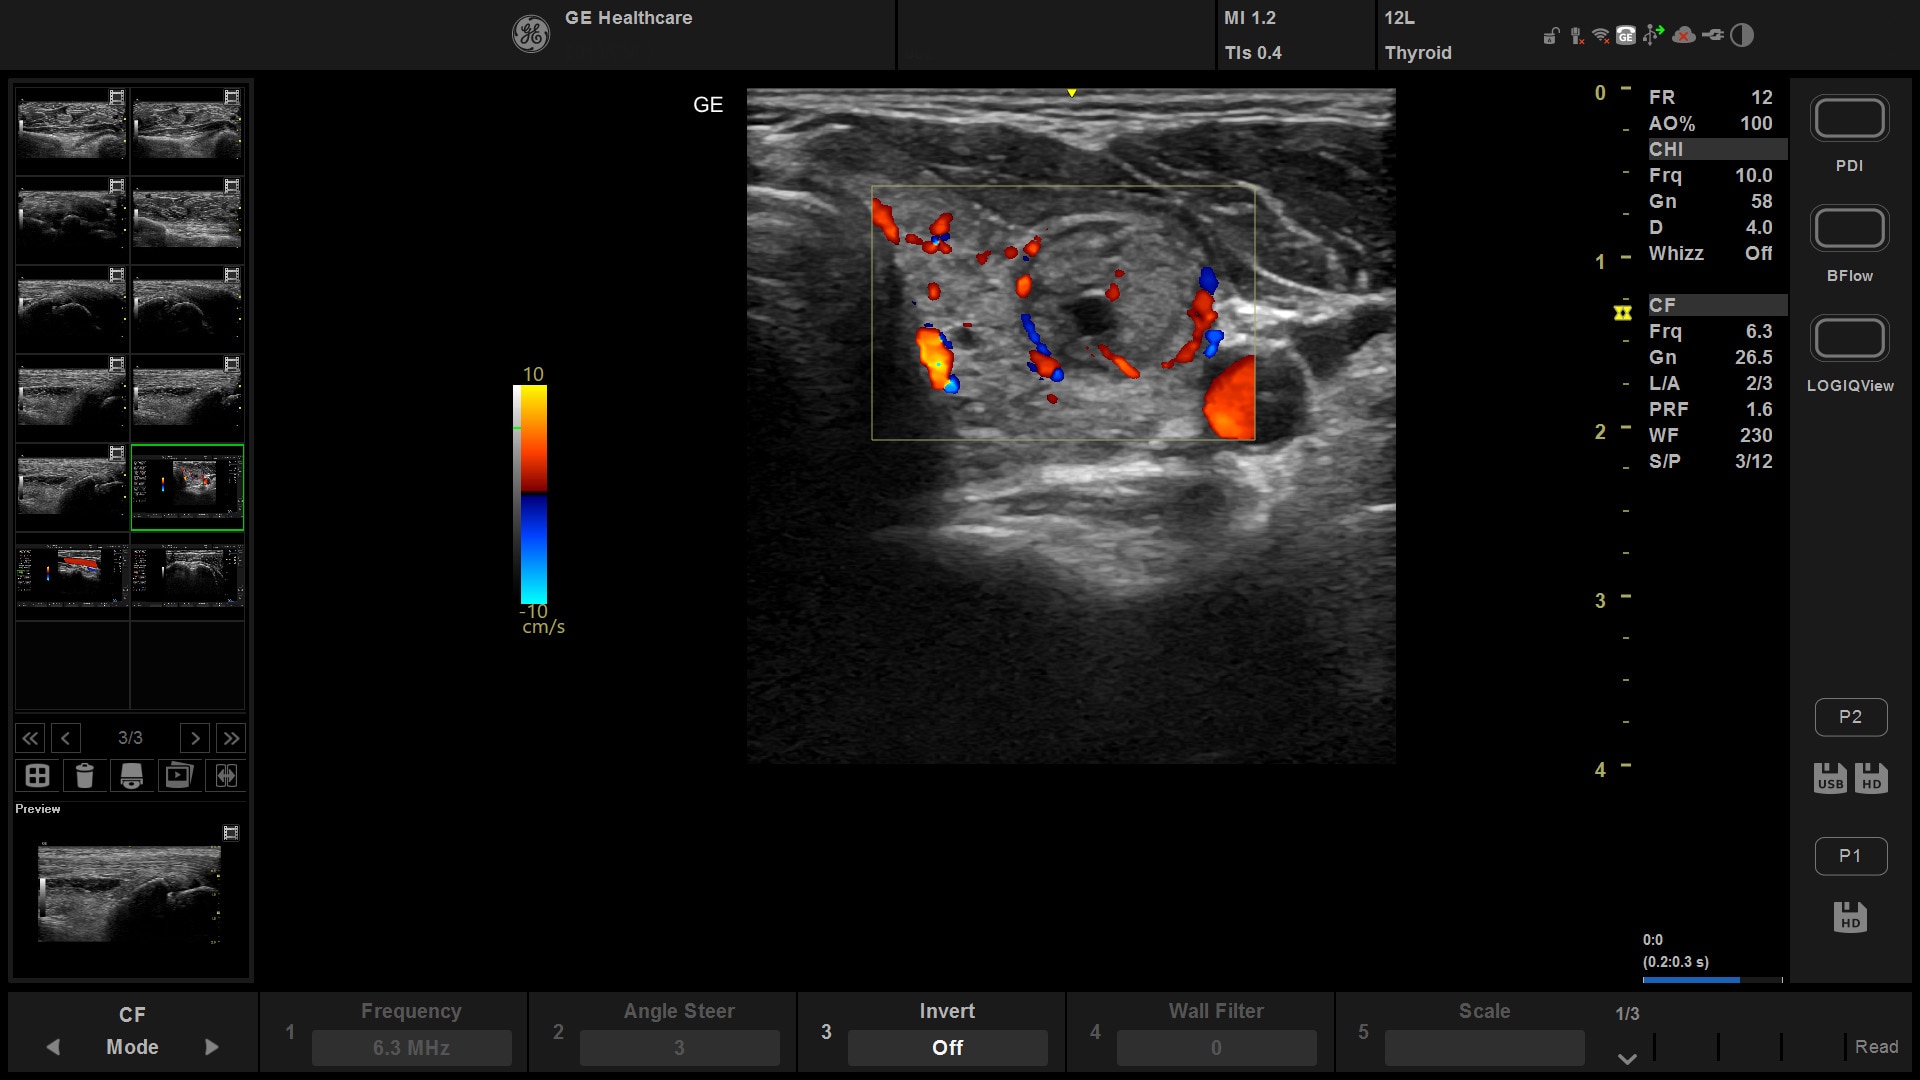

BROAD COVERAGE

A complete solution

Versana Active features a wide range of advanced clinical applications and automated tools that simplify exams, streamline workflow, and enable fast, high-volume scanning to help you diagnose a wide spectrum of patient conditions.